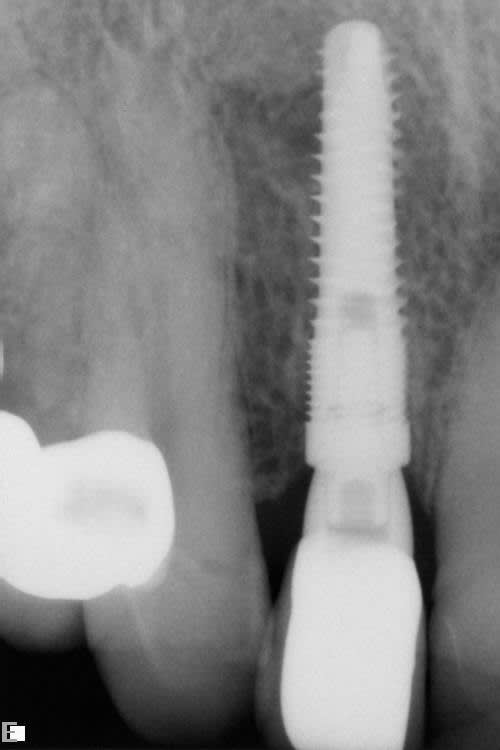

A periapical radiograph (Figure 12) revealed previous endodontic treatment and periapical pathology. After an endodontic specialist consultation and the poor restorative prognosis being established, the patient elected extraction of this tooth and replacement with an immediate implant. Following an extraction procedure that minimized the trauma to the labial portion of the alveolus of tooth No. 7, an osteotomy was prepared using a SICAT CAD/CAM-generated surgical guide (SICAT/Sirona, www.sicat.com), and a 3.8-mm x 16-mm implant (Genesis) was placed with an insertion torque of 45 Ncm (Figure 13). The osteotomy was performed through the apical area of the alveolus and within the palatal wall. An implant–socket gap approximately 1 mm wide and 5 mm in depth was evident on the distal aspect of the osteotomy immediately after implant placement (Figure 14). No bone graft was used in the osteotomy space, as the labial plate thickness was deemed to be about 2 mm, and the distal socket residual wall had a thick (>2 mm), dense lamina dura; this presentation, in the author’s experience, has a high degree of predictability of bone fill.

Figure 15 shows the periapical radiograph at final crown placement (Visit 4). The abutment was screwed in place to a torque of 35 Ncm and the cement-retained crown was placed with RelyX™ Unicem (3MESPE, www.3MESPE.com); at this time only mild gingival inflammation was observed (Figure 16). One year later (18-month follow-up), an excellent esthetic result was observed from the facial aspect, with good tissue tone and no gingival recession (Figure 17).

Three years postoperatively, radiographic interpretation suggested maintenance of the crestal bone level and a stable thickness of the labial plate, from the time of implant placement throughout the follow-up period (Figure 18).